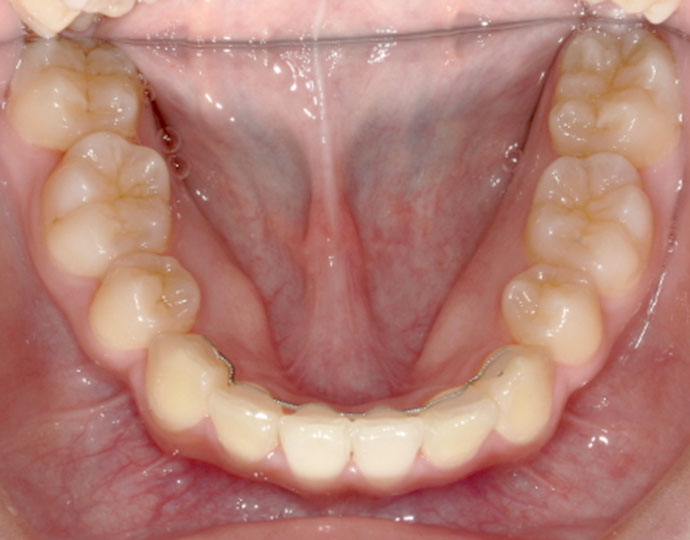

治療後

| 患者様 | 女性 18歳 |

| 主訴 | 歯並びを綺麗にしたい。 |

| 診断 | 叢生歯列不正咬合 |

| 治療方針 | 上下顎左右第一小臼歯の抜歯(計4歯) |

| 治療に使用した装置 | セルフライゲーションブラケット(インタラクティブタイプ) |

| 治療期間 | 2年2カ月 |

| 治療回数 | 24回 |

| 治療費(自費診療) | 847,000円(税込み) |